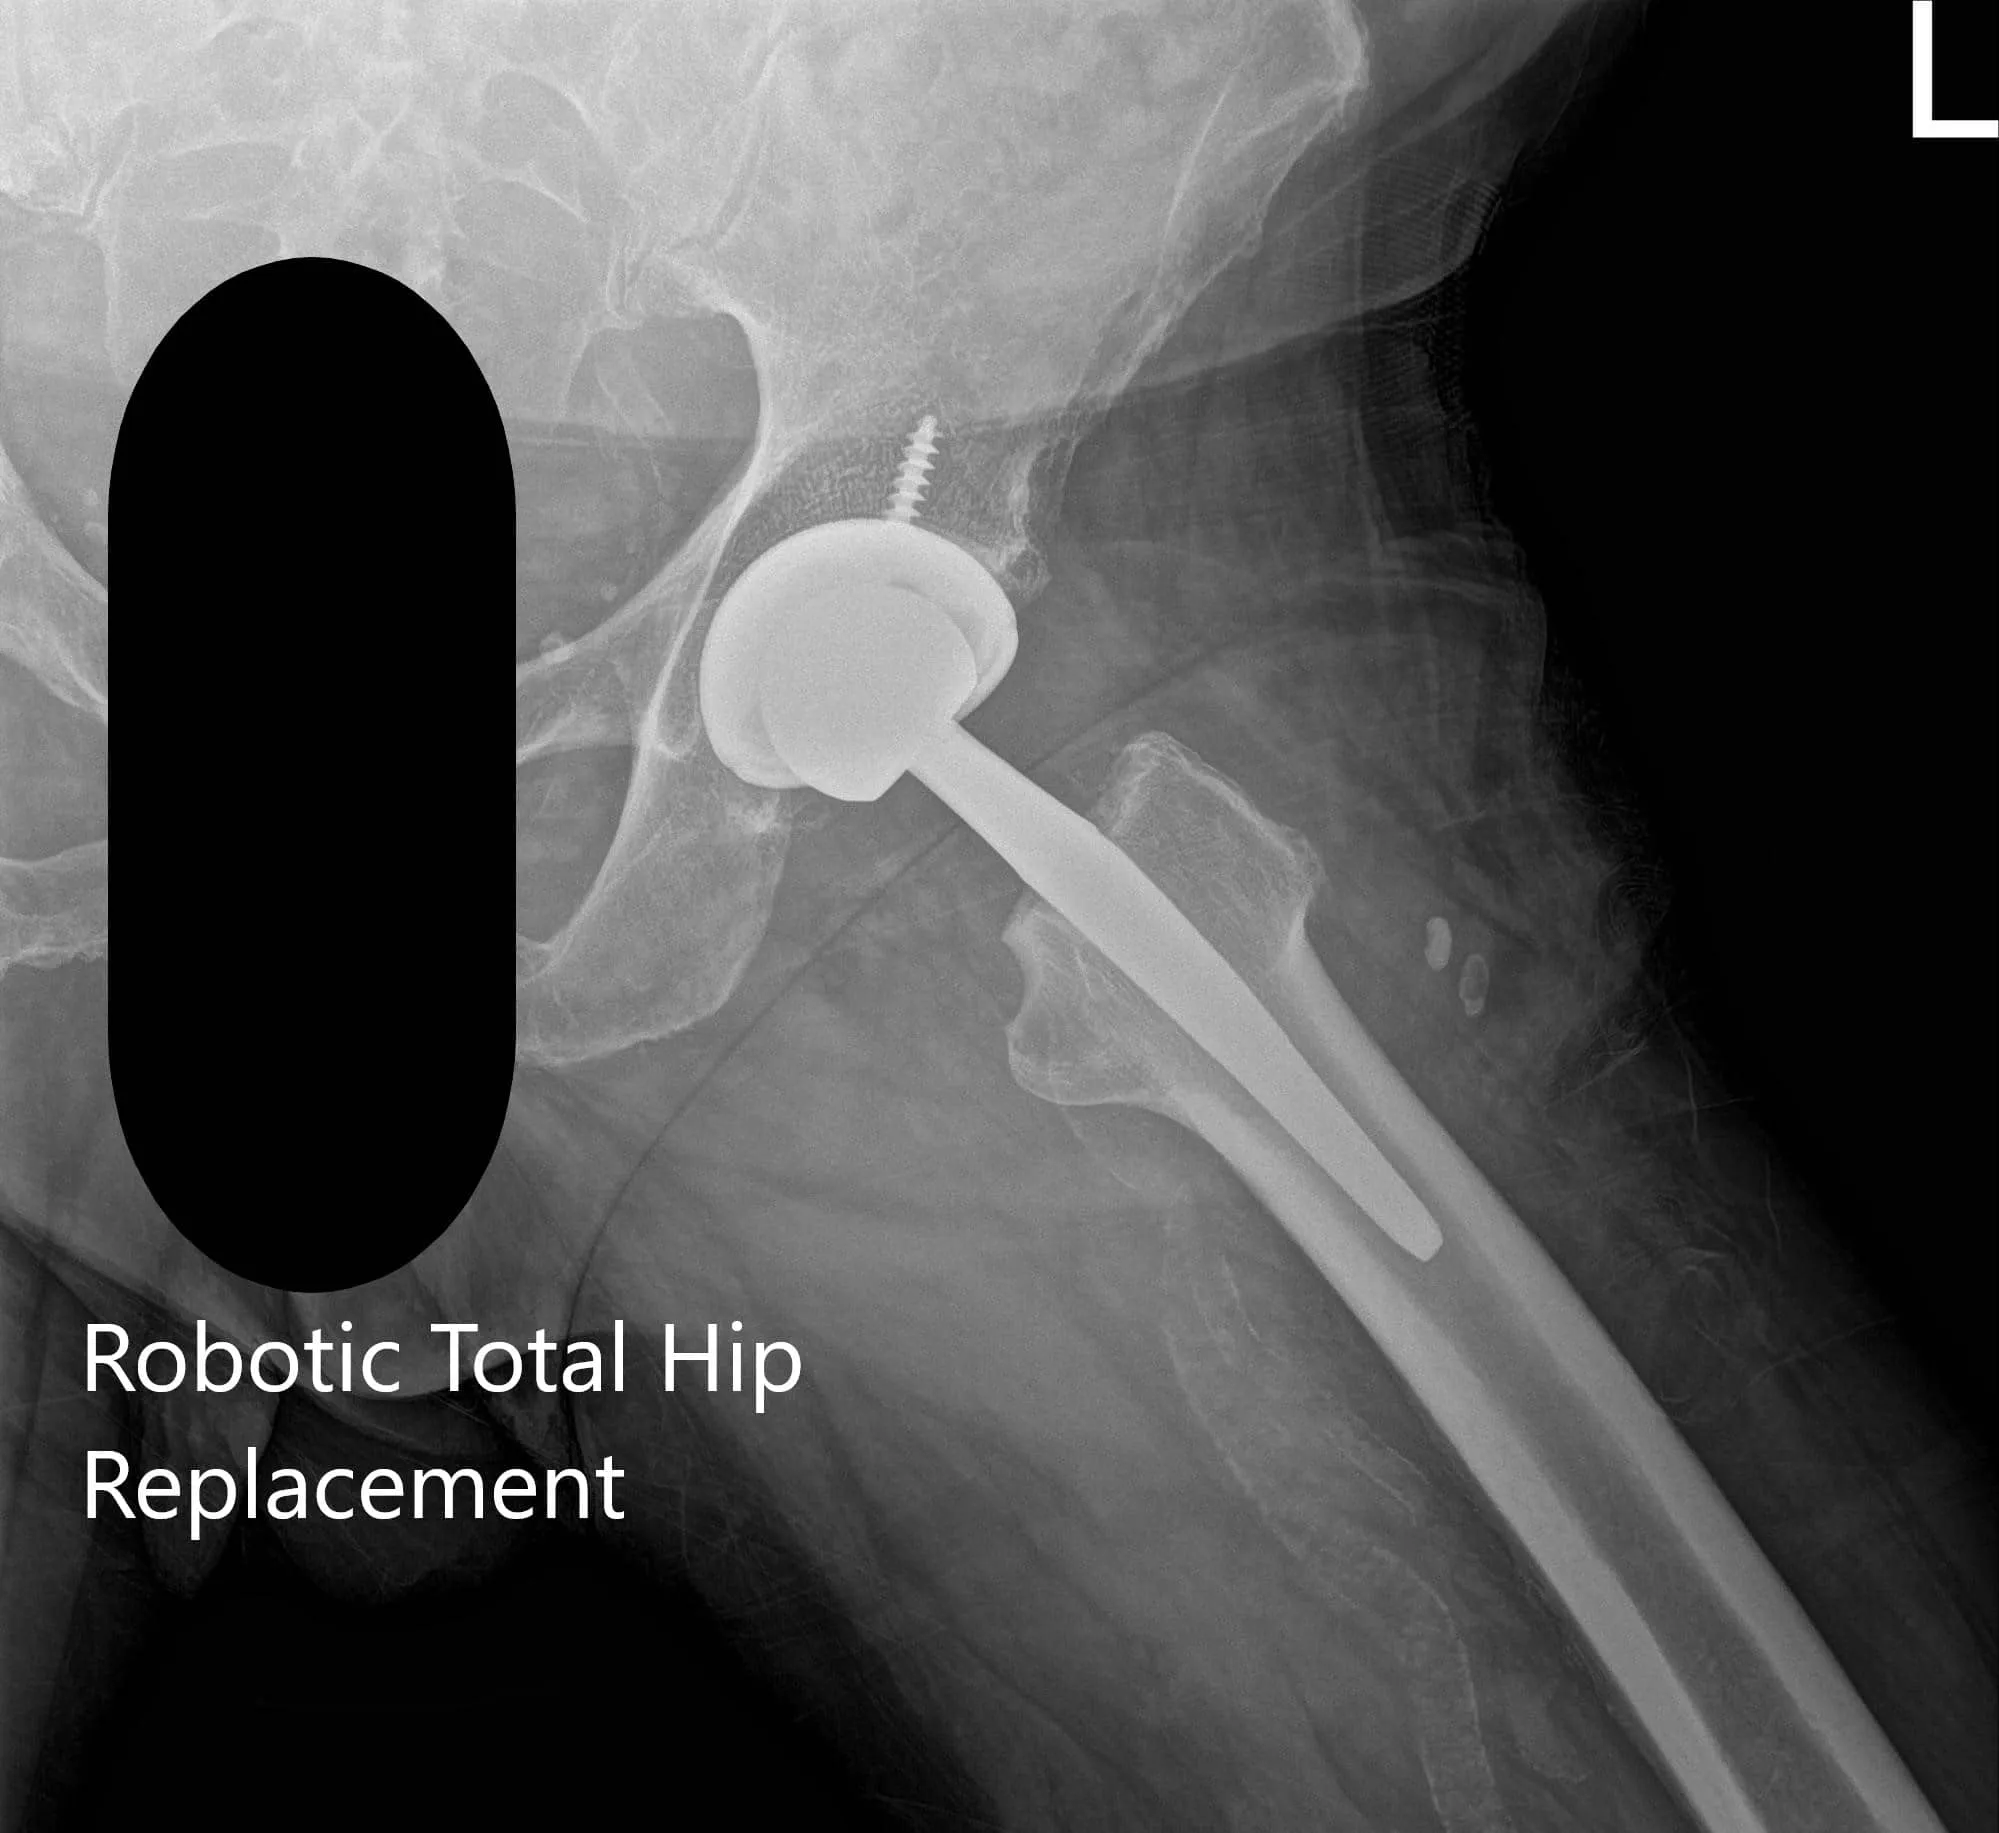

IMPLANTES UTILIZADOS: Cabeza femoral cerámica de 36 mm más 5 con sistema de vástago de cuello de 127 grados tamaño 5 con un orificio de racimo de concha acetabular de 54 mm con inserto de polietileno y tornillo de 25 mm.

Radiografía postoperatoria de la cadera izquierda que muestra visión AP y pata de rana lateral